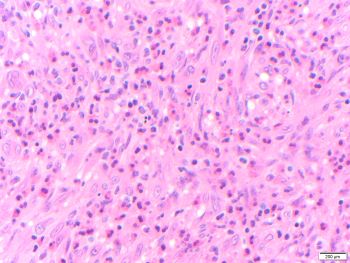

Microscopic sections show a proliferation of well-formed small blood vessels with lobular arrangement and occasionally arranged around small arteries. The small vessels are formed by epithelioid endothelial cells that display abundant eosinophilic cytoplasm and enlarged round nuclei, and normal to low nuclear-to-cytoplasmic ratio; while in more cellular areas the nuclei become elongated. The stroma is hemorrhagic to edematous with mixed inflammatory cells including numerous eosinophils, which may be a clue to the diagnosis in small biopsies.

The tumor cells express endothelial markers such as CD31, CD34, FLI1, ERG and factor VIII-related antigen. In this case, immunohistochemistry was used to demonstrate that the epithelioid endothelial cells were positive for the vascular marker ERG. Most cases show rearrangement of FOS or FOSB. The histopathologic differential diagnosis should include angiosarcoma, which is not typically well demarcated, lacks the lobular architecture, shows more cytologic atypia, and has significant proliferative activity (absent in this case). Metastatic carcinoma is negative for vascular markers. Epithelioid hemangioendothelioma shows hyalinized or chondroid stroma and vacuolated cells